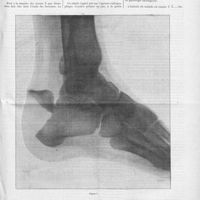

0099 - Page 95 - Anatomie pathologique de la tuberculose pleurale. Par M. A.-N. Peron... Réactions organiques locales consécutives / Traitement du pied bot congénital. D'après le Professeur Sprengel0099 - Page 95 - Anatomie pathologique de la tuberculose pleurale. Par M. A.-N. Peron... Réactions organiques locales consécutives / Traitement du pied bot congénital. D'après le Professeur Sprengel

0100 - Page 96 - Traitement du pied bot congénital. D'après le Professeur Sprengel [M. Nageotte-Wilbouchewitch] / Analyses. Neurologie et psychiatrie. Hoffmann. Nouvelle contribution à l'étude de l'atrophie musculaire progressive héréditaire dans l'enfance (Deutsche Zeitchrift für Nervenheilkunde, 1897...) [G. Marinesco]0100 - Page 96 - Traitement du pied bot congénital. D'après le Professeur Sprengel [M. Nageotte-Wilbouchewitch] / Analyses. Neurologie et psychiatrie. Hoffmann. Nouvelle contribution à l'étude de l'atrophie musculaire progressive héréditaire dans l'enfance (Deutsche Zeitchrift für Nervenheilkunde, 1897...) [G. Marinesco]